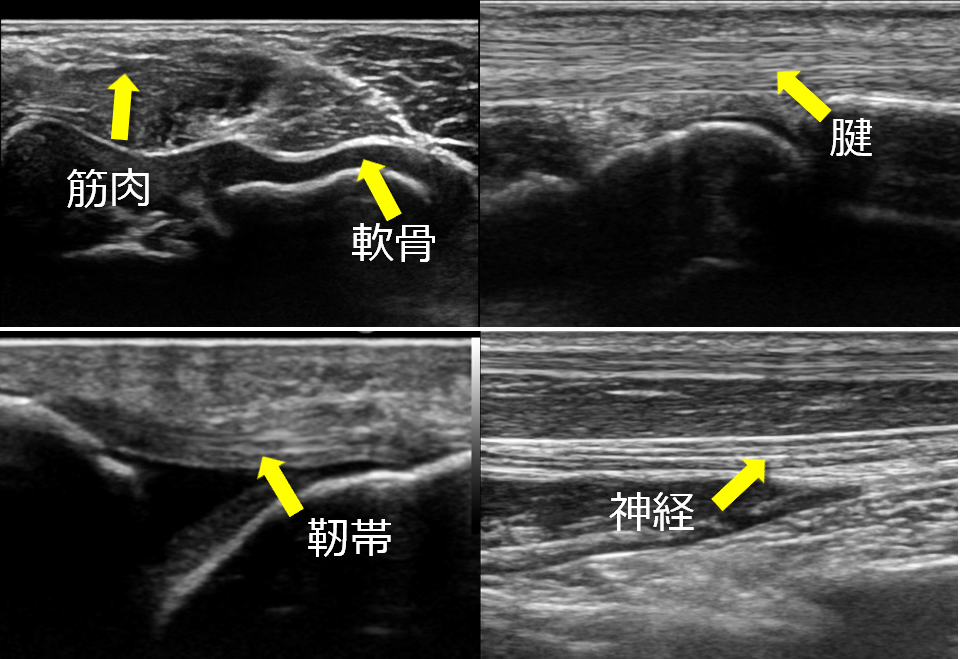

一般的に整形外科というとレントゲンのイメージ強いかと思いますが、超音波を用いることで、レントゲンでは見ることが出来ない、骨以外の軟骨、神経、筋肉、腱、靭帯、血管などを確認し、さらにリアルタイムで血流や動きを観察することが可能になります。